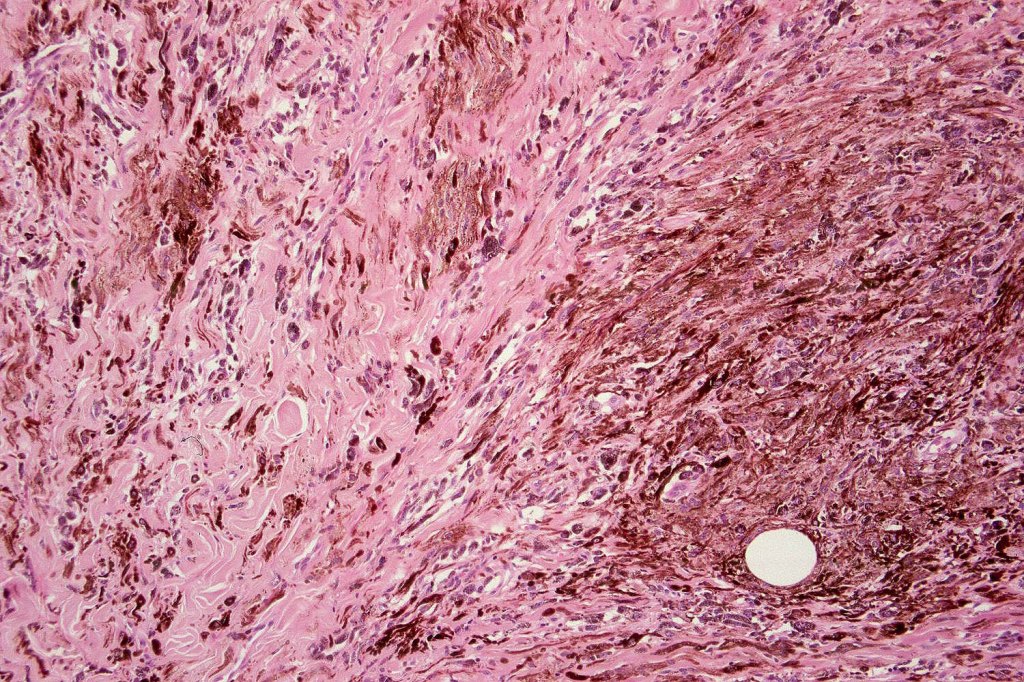

•Admixture of spindle cells, pigmented bipolar or dendritic cells & melanophages

•Cytoplasm is pale and nuclei are small with inconspicuous nucleoli

•Some tumors are composed spindle cells in a fascicular or neuronevoid pattern